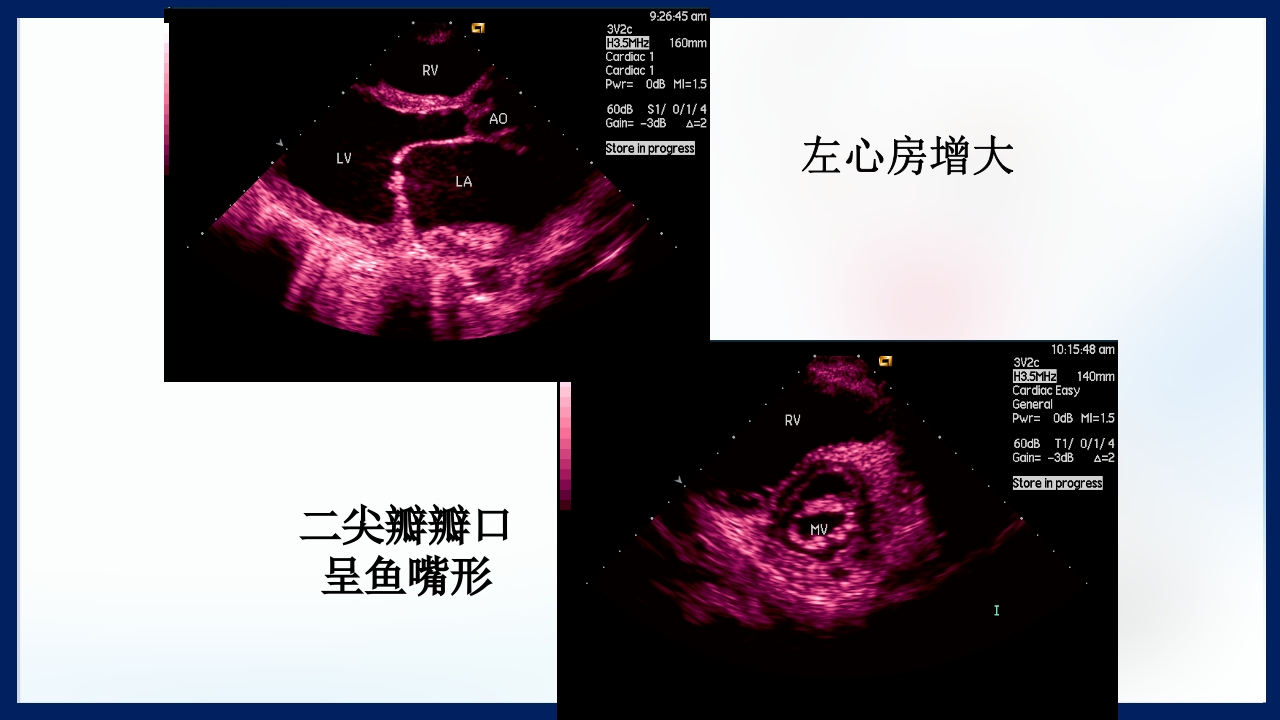

心 脏 瓣膜 医师:XXX 日期:20XX.XX.XX 讲授目的和要求 1 掌握二尖瓣和主动脉瓣膜病变的病理生理、临床表现及诊断方法。 熟悉二尖瓣和主动脉瓣膜病变的病因、鉴别诊断、并发症、治疗原则及 2 手术适应证。 3 了解瓣膜病的检查方法及治疗新进展。 心脏瓣膜病 是由于炎症、粘液样变性、退行性改变等原 因引起的单个或多个瓣膜结构的功能或结构异常,导致 瓣口狭窄及(或)关闭不全。二尖瓣最常受累,其次为 主动脉瓣。 (Rheumatic Heart Disease)简称风心病, 是风湿性炎症过程所致瓣膜损害,主要累及40岁以下人 群。 瓣膜粘液样变性和老年瓣膜钙化所致瓣膜病日渐增多。 3 瓣膜病分类 按病因分类: 风湿性、老年退行性、先天性、相对性 按受累部位和类型分: 二尖瓣狭窄、二尖瓣关闭...